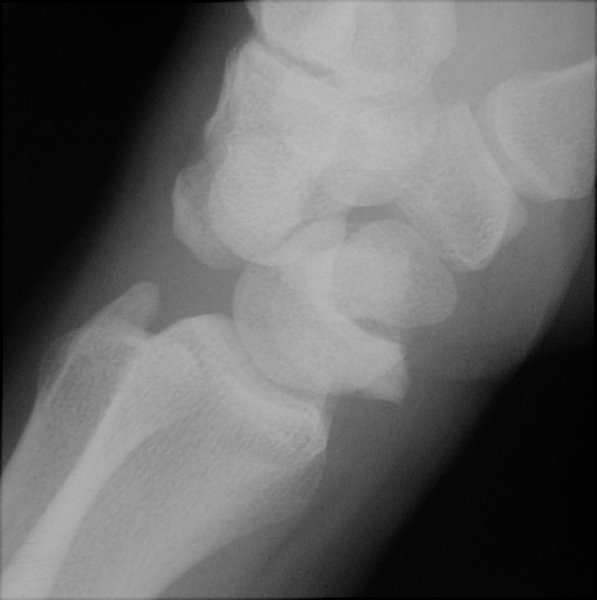

Return to Perilunate Dislocation